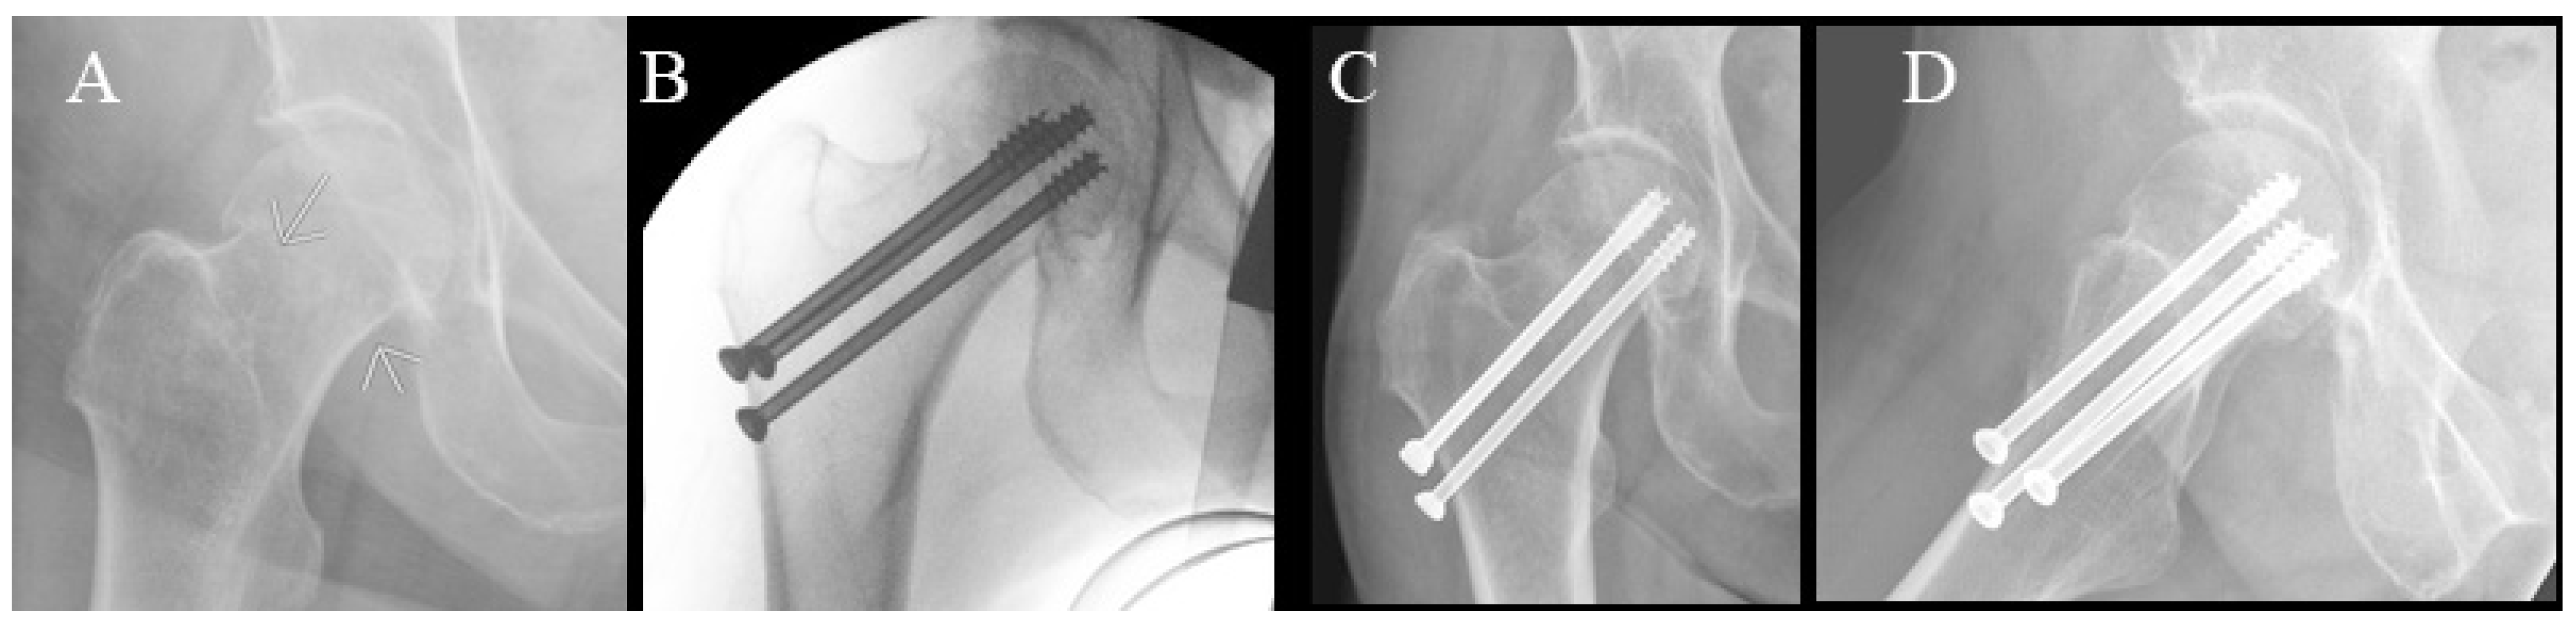

Figure 5.

Radiographs of cannulated hip screw fixation with three screws. (A) Preoperative radiograph. (B) Perioperative radiograph. (C) Anteroposterior radiograph at 6-week follow-up. (D) Lateral radiograph at 6-week follow-up.